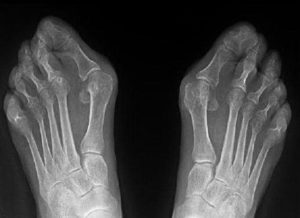

Вальгусная деформация стопы у взрослых выглядит весьма удручающе. Это стопы, которые будто заваливаются внутрь. Пятки разделены внушительным расстоянием (более четырех сантиметров) при сведенных вместе и выпрямленных ногах. Сами стопы уплощаются и при ходьбе возникают исключительно неприятные ощущения.

При вальгусе образуется определенное искривление x-образной формы. Внутренний край пятки опирается на поверхность. В то же время начинает выпирать косточка около большого пальца ноги внутрь стопы. Чаще всего дефект сопровождается плоскостопием.

Вальгусная стопа у взрослых может быть одной из трех различных степеней тяжести:

- Первая степень. Ярко выраженной деформации стопы не наблюдается, пациент легко передвигается и хорошо себя чувствует. Однако, при длительной ходьбе начинает испытывать сильные болевые и деформирующие ощущения. Это один из первых тревожных сигналов, требующий реакции и профилактических действий, которые избавят от развития болезни ног.

- Вторая степень. Внешне форма стопы начинает отличаться, но не критично. Виден небольшой нарост, а косточка увеличена. Выбрать обувь становится проблематично. Если отреагировать на этом этапе, то лечение будет заключаться в массажах, ванночках и компрессах с травами, специальными упражнениями и ортопедической обувью, стопа становится практически плоская. Если не реагировать – болезнь перейдет в последнюю стадию.

- Третья степень. Нога выглядит крайне не эстетично, она обретает не природную форму. Сильно выражен нарост и косточка около большого пальца, а сам палец располагается не ровно и деформируется. Боль преследует при каждой попытке пройтись, а подобрать обувь – практически не представляется возможным. Но даже в мягкой не давящей обуви, очевидно, просматривается проблема. На этой стадии консервативное лечение уже не целесообразно, поэтому чаще всего применяется хирургическое вмешательство. И на вопрос: как лечить вальгусную деформацию на этой стадии, любой врач ответит – только в стационаре. Само вмешательство является сложной операцией с тяжелым послеоперационным периодом. В не самых запущенных случаях справиться с недугом сначала пытаются комплексом мероприятий, обычно применяемых при диагностированной второй стадии.

Вальгусная деформация стоп – дефект стопы, характеризующийся снижением высоты ее сводов и Х-образным искривлением оси. Расстояние между внутренними краями лодыжек составляет более 4-5 см, при этом пятка и пальцы отклоняются к внешней стороне, а внутренние своды стоп «заваливаются» внутрь.